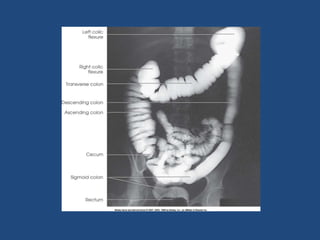

BARIUM ENEMA

• LARGE BOWEL EXAMINATION

TECHNIQUE

• Perform P/R examination

• Insert enema tip with patient in lt lateral position

with knees flexed

• Check for any blocks

• Look intermittently under flouroscopy to check for

progression of Ba column

• Gas insufflation done intermitently

• change position of patient and table accordingly

SPOT FILMS

• Rectum & sigmoid colon-RAO in lying position

• Splenic flexure-LAO(erect)

• Hepatic flexure-RAO(erect)

• Caecum-supine lying on rt side with head down tilt

and compression

• Over head film- lying position